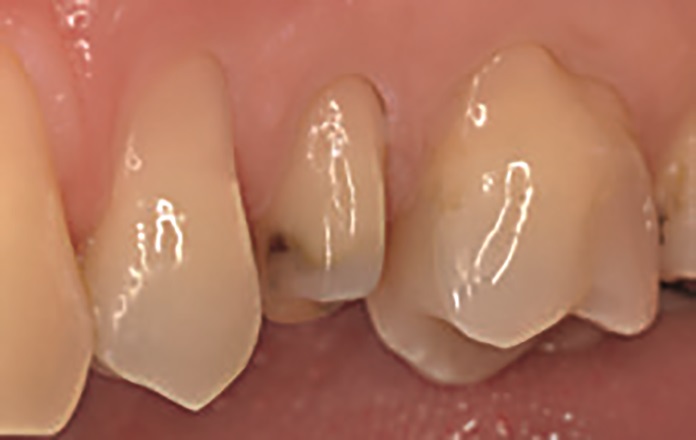

47‑letnia pacjentka zgłosiła się z powodu objawów zapalenia miazgi zęba 15. W badaniu wewnątrzustnym stwierdzono obecność starego wypełnienia amalgamatowego oraz złamanie guzka policzkowego zęba 15 (ryc. 1 i 2). W związku z tym na pierwszej wizycie przeprowadzono leczenie endodontyczne zęba 15 w znieczuleniu miejscowym (ryc. 3).